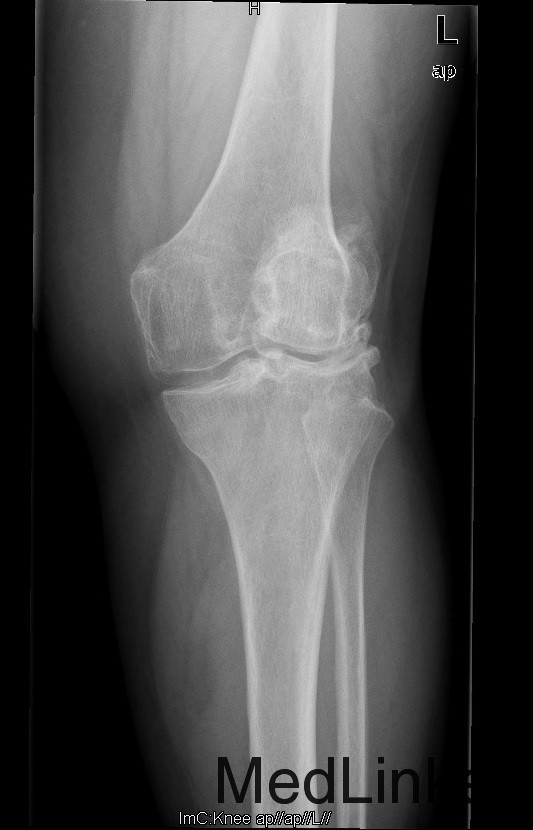

查体:步态跛行,双膝屈曲畸形,左膝外翻、右膝内翻畸形,双膝内外侧关节间隙及髌股关节间隙压痛明显,右侧重,右膝内翻:5°,右膝屈70°,伸-10°;左膝:屈曲:100°,伸:-5°,外翻:20°,双膝主被动屈伸活动时疼痛,双膝髌下摩擦音(+)。 辅助检查:右膝关节间隙狭窄,软骨下骨硬化,髌股关节间隙消失,左膝关节间隙狭窄,软骨下骨硬化,髌股关节间隙狭窄,双膝髌骨、股骨、胫骨周围大量骨赘形成,关节腔内均可见游离体。

诊断:1.双膝重度骨关节炎继发右膝屈曲内翻畸形,左膝屈曲外翻畸形(Krackow Ⅰ型)2.高血压病(3级 极高危) 治疗:积极行术前准备,待血压等稳定后于全麻下行右侧全膝关节置换术,术后常规治疗,并鼓励其锻炼。